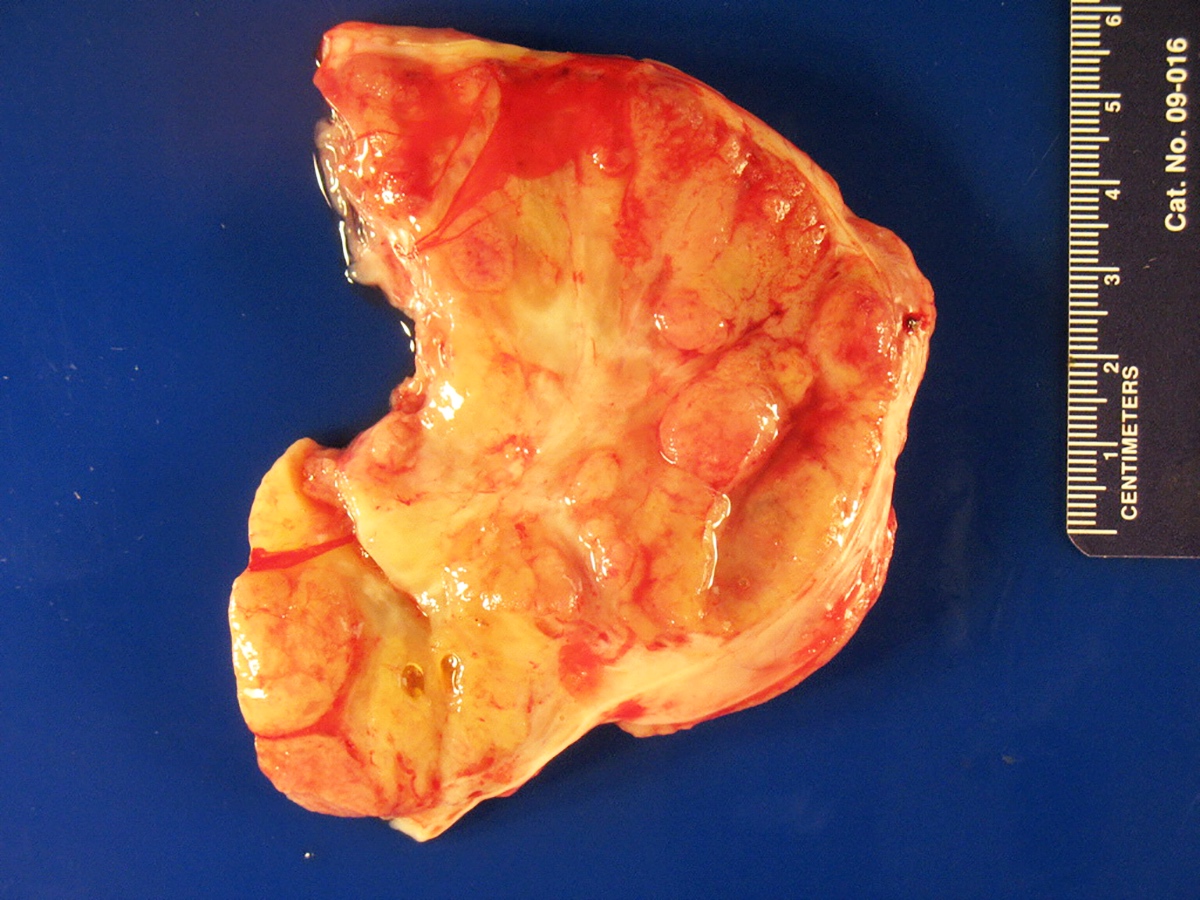

Gross description

- Almost always unilateral (Am J Surg Pathol 1985;9:543)

- Tumor size ranges widely from < 1 cm to 35 cm (mean 12 - 14 cm) (Am J Surg Pathol 1985;9:543)

- Cut surface is typically solid, tan-yellow

- Cystic component may also be seen, especially in tumors with heterologous elements or with a retiform morphologic pattern

- Poorly differentiated tumor may show grossly identifiable foci of necrosis